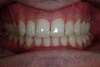

Fin de traitement